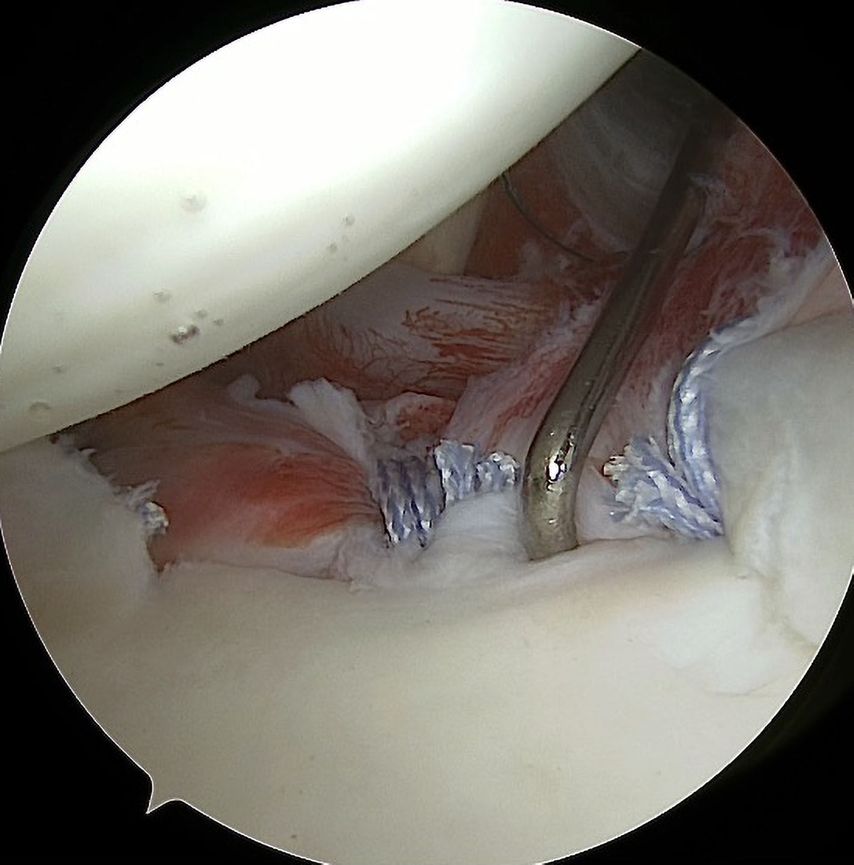

Zusätzlich zur Kapsel-Labrum-Refixation wird in zunehmendem Maße eine Remplissage (unanatomische Kapsulotenodese der Infraspinatussehne) empfohlen, dies insbesondere bei Revisionseingriffen, bei sehr sportlichen Patienten, besonders Kontaktsportlern und Patienten mit hohem funktionellem Anspruch und einer hohen Rezidivgefahr57,58 (Abb. 4a, 4b). Ursprünglich für Patienten mit großen Hill-Sachs-Defekten empfohlen („off-track“ Läsionen), ist in jüngerer Zeit eine deutlich großzügigere Indikationsstellung zur Remplissage auch bei „on-track“ Läsionen festzustellen.59 Für arthroskopische Bankartoperationen mit zusätzlicher Remplissage sind deutlich geringere Versagerraten und bessere Sportfähigkeit beschrieben.60 Die früher beklagte signifikante Einschränkung der Beweglichkeit nach einer Remplissage konnte in der neueren Literatur nicht bestätigt werden.61

Abb. 4a, b: Zusätzlich zur Kapsel-Labrum-Refixation wird in zunehmendem Maße eine Remplissage empfohlen, dies insbesondere bei Revisionseingriffen, bei sehr sportlichen Patienten mit hohem funktionellem Anspruch und einer hohen Rezidivgefahr